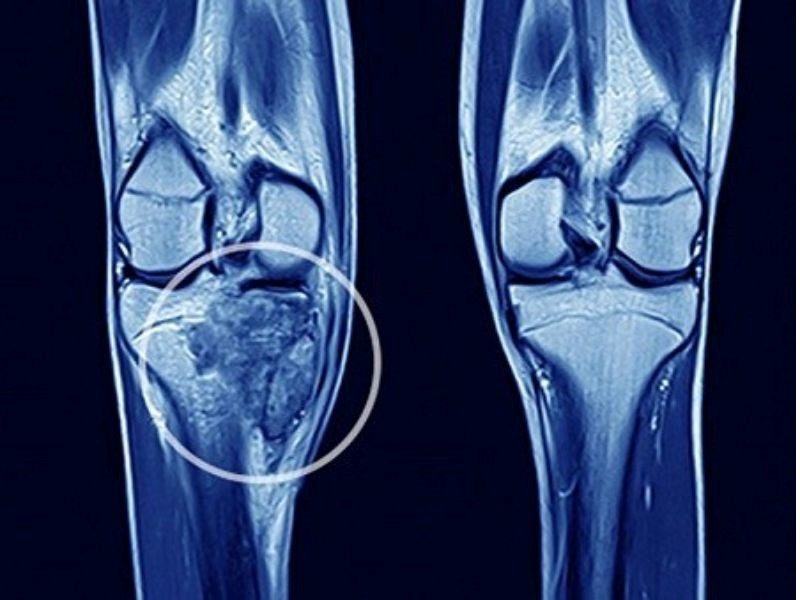

Biến dạng xương và sưng phồng

Khi khối u phát triển lớn và nằm gần bề mặt da, chúng có thể gây ra sự biến dạng xương hoặc tạo ra hiện tượng sưng phồng rõ rệt. Ngoài ra, các biến chứng như hoại tử hoặc nhiễm trùng cũng có thể làm gia tăng cảm giác đau đớn. Đặc biệt, nếu ung thư xương xảy ra ở vùng cột sống cổ, nó có thể chèn ép vào các cấu trúc xung quanh, gây ra các vấn đề như khó nuốt hoặc khó thở.